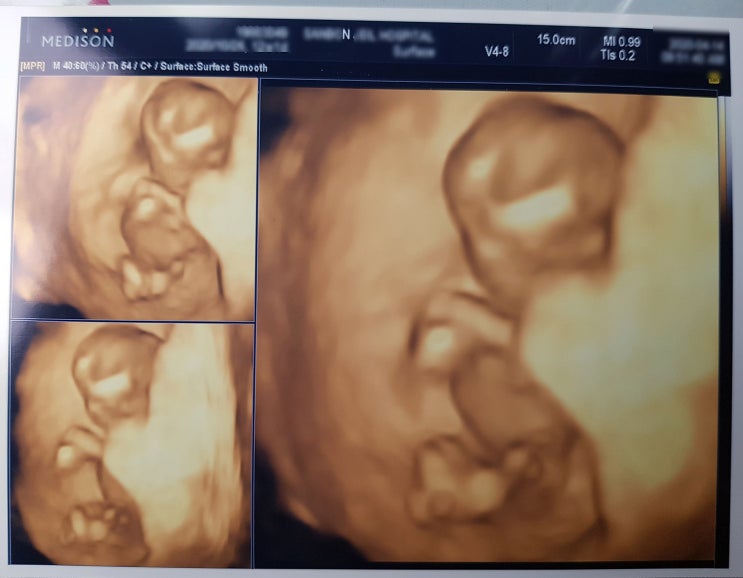

[임신12주차/5.2cm] 임신12주증상, 12주 입덧, 12주차 검사, 1차 기형아 검사, 12주 배크기, 끝날듯 안끝나는 입덧

태교일기 임신 12주차에 정밀초음파 검진 내원했어요 머리부터 엉덩이까지 길이는 5.2cm 목투명대 검사 1.1...